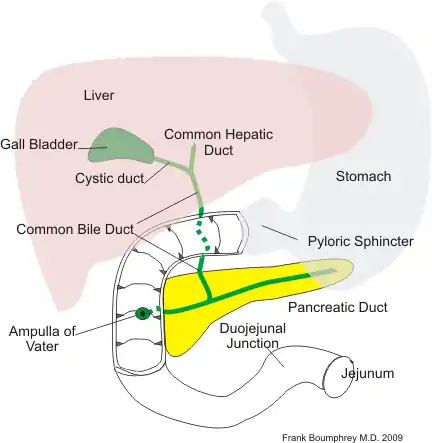

The duodenum is itself divided into three parts: the first, second, and third part. Small portions of highly acidic chyme is released into the first part of the duodenum. This part secretes the hormone secretin from the mucosal cells (as do the other parts of the doudenum) in response to the presence of acidic chyme leaving the stomach. This stimulates the pancreas to secrete copious amounts of neutralizing sodium bicarbonate, so the pH of the chyme is nearer 7 when it leaves the duodenum. The digestive enzymes of the pancreas and small intestine operate maximally at this pH. This also means that any pepsin from the stomach is also deactivated. The first part of the duodenum does not have plicae and folds, indicating that this part is probably not important for absorption.

In the second part of the duodenum bile and pancreatic enzymes are secreted via the common duct into the lumen see (Biliary System & Pancreas) below. Absorption of food starts in the second part of the duodenum.

Biliary System & Pancreas

Bile and bile salts are manufactured by the liver and fed into the second part of the duodenum via the common duct. Bile salts are important in fat digestion.

The pancreas is a retro-peritoneal gland that is both an endocrine gland (producing the hormones insulin and glucagon) and an exocrine gland (producing digestive enzymes). The enzymes are secreted in a deactivated form - to prevent auto-digestion - and are activated in the lumen of the duodenum.

The following illustration indicates the relationships of the pancreas and biliary systems.